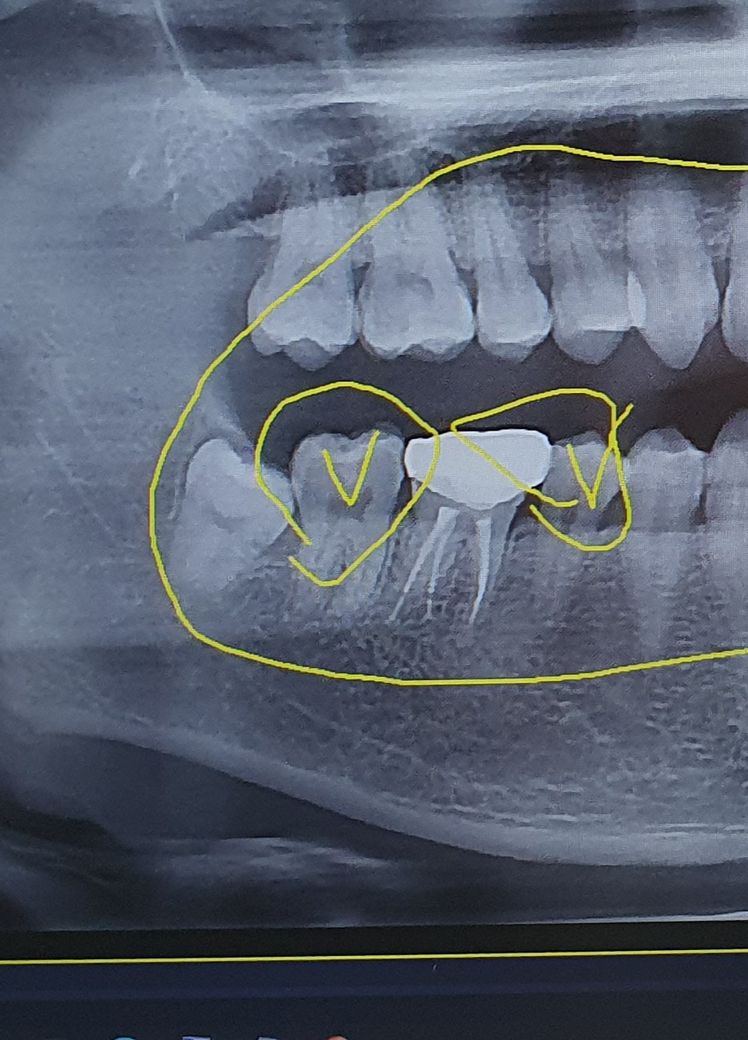

사랑니 이거 낭종인가요? 병원에서 미처 못물어봄

원래는 사랑니부근에 계속 이상한 맛과 냄새가나서 빼러 갔었는데 충치도 좀 있어서

사랑니 먼저 빼면 힘들거라고 충치부터 치료 하자며

사랑니에는 염증이 생긴거라 하더라고요 ....

염증이랑. 낭종이랑 다른거죠? 그리고 저거 빨리 치료 안해도 되나요? 먼가 빈공간이 염증이면 저것도 같이 치료해주나요?사랑니는 빼는게 좋다 하셨는데 큰 수술인가요(걱정)